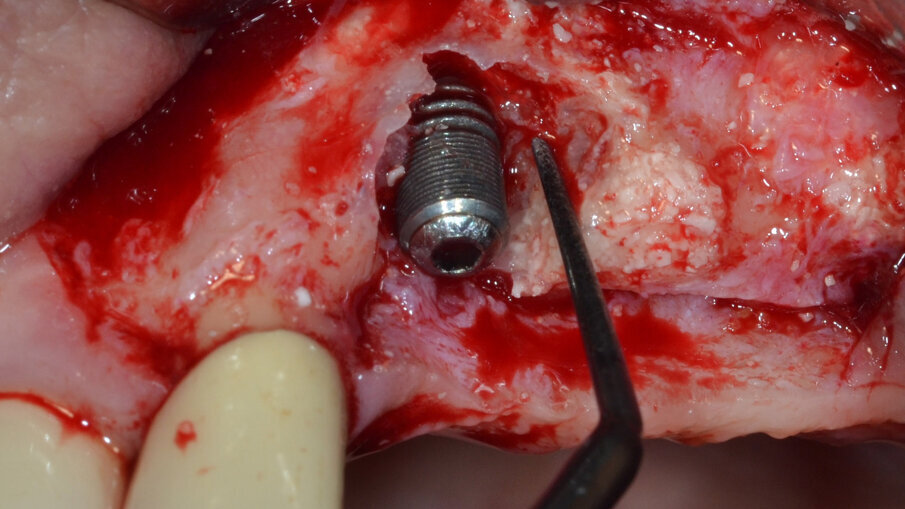

Al termine di questa procedura si rimuove la vite di copertura allo scopo di decontaminare anche la superficie interna dell’impianto mediante il dispositivo a cavitazione ultrasonica (PIEZOCLEAN by Dr. Giacomo Tarquini, Esacrom). Il dispositivo a cavitazione ultrasonica “PIEZOCLEAN by Dr. Giacomo Tarquini” è composto da un inserto metallico (da collegarsi a un manipolo a ultrasuoni) dotato di appositi micro-fori per favorire la diffusione del liquido irrigante (ES004E, Esacrom) e da una camera di cavitazione (PIEZOCLEAN by Dr. Giacomo Tarquini, Esacrom) realizzata in silicone di grado medicale appositamente disegnata per consentire un adattamento ottimale alla morfologia dell’osso crestale (Fig. 6).

Fig. 6 - Dispositivo per cavitazione ultrasonica “PIEZOCLEAN by Dr. Giacomo Tarquini” applicazione del dispositivo “PIEZOCLEAN by Dr. Giacomo Tarquini” e decontaminazione completa dell’impianto.